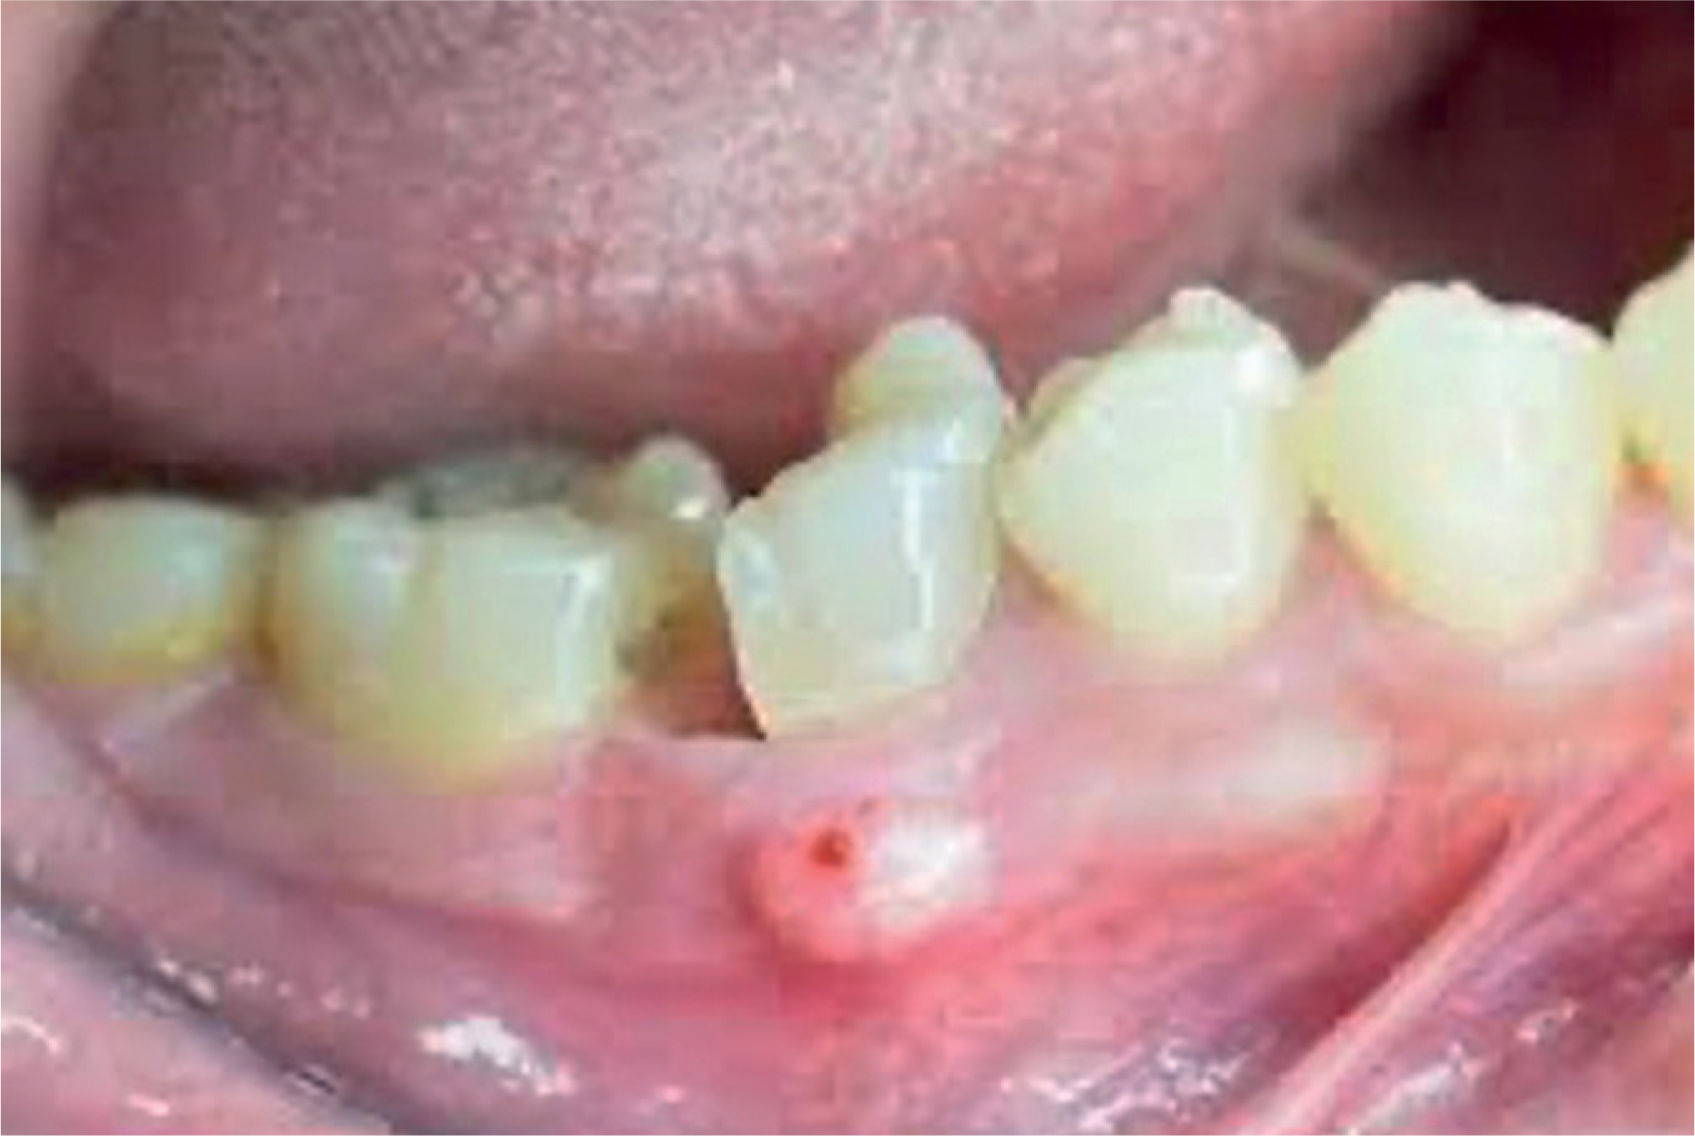

Absceso gingival: doloroso, localizado en la encía marginal e interdental, generalmente asociado al impacto de cuerpos extraños (fig. 8).

Absceso periapical o dentoalveolar: afecta a los tejidos circundantes a la raíz dental tras la afectación pulpar originada por una caries. Puede cursar con exudado purulento. Se caracteriza por dolor intenso, constante y a la percusión de la pieza dental afectada dolorosa. Es característica la sensación de «diente largo» (el paciente refiere que el diente le ha crecido) (fig. 9).

Absceso periodontal: al alcanzar la pared gingival de una bolsa profunda periodontal. Puede cursar de forma aguda o cronificarse. Puede ser asintomático si drena espontáneamente (fig. 10).